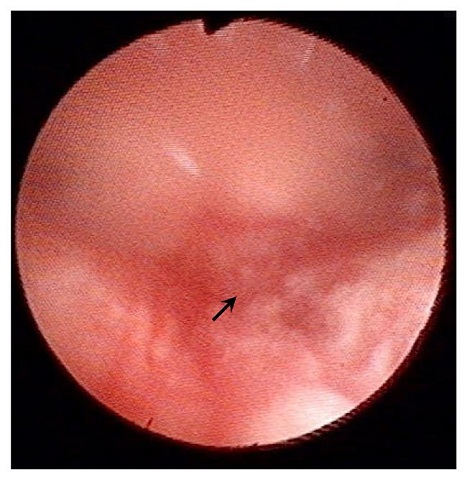

內膜薄沒有關係!子宮內膜不到0.7公分(如0.4公分、0.5公分),懷孕率62.5%(

發表在台灣生殖醫學會2016年年會得研究報告

台中榮總的大規模405人研究)

2016.08.12

子宮內膜刺激手術 2016 最新 國際認證 證明 是可以增加試管嬰兒成功率胚胎著床率,但是大部分病人會痛However, the endometrial injur...